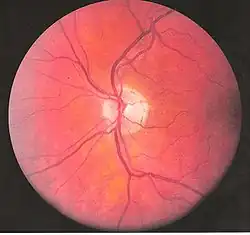

Interior of posterior half of bulb of left eye. The veins are darker in appearance than the arteries. (Central retinal artery visible but not labeled).

Interior of posterior half of bulb of left eye. The veins are darker in appearance than the arteries. (Central retinal artery visible but not labeled). -

Thus if the central retinal artery gets occluded, there is complete loss of vision in that eye even though the fovea is not affected. The entire retina (with the exception of the fovea) becomes pale and swollen and opaque while the central fovea still appears reddish (this is because the choroid color shows through). This is the basis of the famous "Cherry red spot" seen on examination of the retina on funduscopy of a central retinal artery occlusion (CRAO).